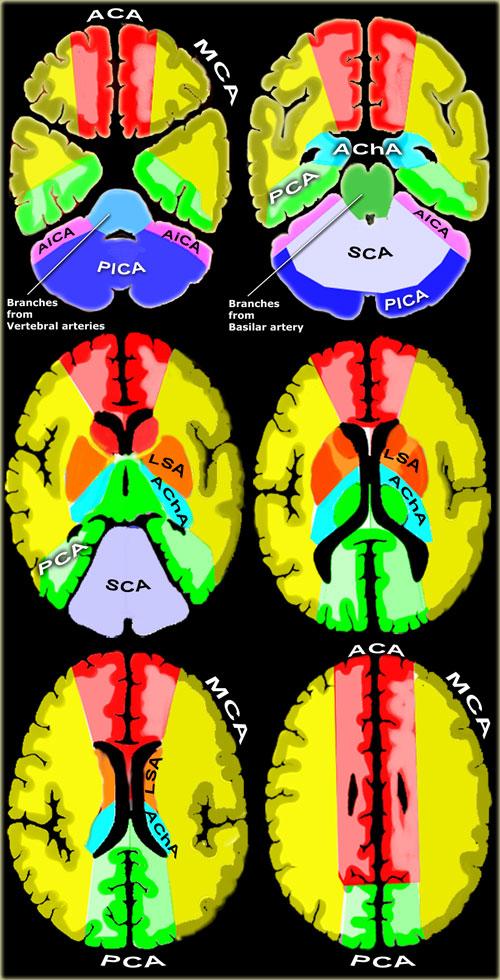

Vùng tưới máu của các động mạch não (được điều chỉnh và sửa đổi với sự cho phép của M. Savoiardo (1)

- Động mạch tiểu não sau dưới (PICA – màu xanh lam)

Vùng tưới máu của PICA nằm ở mặt chẩm dưới của tiểu não và cân bằng với vùng tưới máu của AICA (màu tím), vốn nằm ở mặt bên (1).

Vùng tưới máu của PICA càng lớn thì vùng tưới máu của AICA càng nhỏ và ngược lại. - Động mạch tiểu não trên (SCA – màu xám)

Vùng tưới máu của SCA nằm ở mặt trên và mặt lều của tiểu não. - Các nhánh từ động mạch đốt sống và động mạch nền

Các nhánh này cấp máu cho hành não (màu xanh lam) và cầu não (màu xanh lá). - Động mạch mạch mạc trước (AchA – màu xanh lam)

Vùng tưới máu của AChA bao gồm một phần hồi hải mã, cánh tay sau của bao trong và kéo dài lên trên đến vùng nằm bên ngoài phần sau của cella media. - Các động mạch thấu kính – vân

Các động mạch thấu kính – vân bên (màu cam) là các động mạch xuyên sâu của động mạch não giữa (MCA).

Vùng tưới máu của chúng bao gồm phần lớn các nhân nền.

Các động mạch thấu kính – vân giữa (màu đỏ đậm) xuất phát từ động mạch não trước (thường là đoạn A1).

Động mạch Heubner là động mạch thấu kính – vân giữa lớn nhất, cấp máu cho phần trước trong của đầu nhân đuôi và phần trước dưới của bao trong. - Động mạch não trước (ACA – màu đỏ)

ACA cấp máu cho phần trong của thùy trán và thùy đỉnh, phần trước của thể chai, nhân nền và bao trong. - Động mạch não giữa (MCA – màu vàng)

Các nhánh vỏ não của MCA cấp máu cho mặt ngoài của bán cầu đại não, ngoại trừ phần trong của thùy trán và thùy đỉnh (thuộc vùng tưới máu của động mạch não trước) và phần dưới của thùy thái dương (thuộc vùng tưới máu của động mạch não sau).

Các nhánh xuyên sâu thấu kính – vân đã được đề cập ở trên. - Động mạch não sau (PCA – màu xanh lá)

Đoạn P1 kéo dài từ nguyên ủy của PCA đến động mạch thông sau, tham gia vào đa giác Willis.

Các động mạch xuyên đồi thị sau tách ra từ đoạn P1 và cấp máu cho trung não và đồi thị.

Các nhánh vỏ não của PCA cấp máu cho phần dưới trong của thùy thái dương, cực chẩm, vỏ não thị giác và gối thể chai.